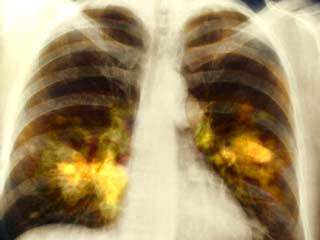

फेफड़ों का कैंसर (Lung Cancer) दुनिया भर में पुरुषों में होने वाला सबसे आम कैंसर था, 2018 में डाइग्‍नोज किए गए नए मामलों की कुल संख्या का 15.5% योगदान करते हैं। मुख्‍य रूप से तीन- फेफड़े, प्रोस्टेट और कोलोरेक्टल कैंसर, सभी कैंसर का 44.4% योगदान करते हैं (गैर-मेलेनोमा त्वचा कैंसर को छोड़कर)। इन आंकड़ों में 5% से अधिक योगदान देने वाले अन्य सामान्य कैंसर पेट और लिवर थे।

• फेफड़े का कैंस (20.9 लाख मामले)

• फेफड़े का कैंसर (17.6 लाख मौतें)